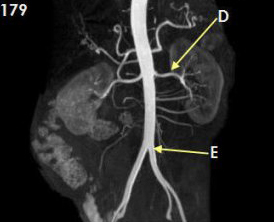

Letter A in Image 179 is pointing to

Right renal artery

Letter B in Image 179 is pointing to:

Branches of mesenteric artery

: Letter C in Image 179 is pointing to

External iliac artery

Letter D in Image 179 is pointing to

Left renal artery